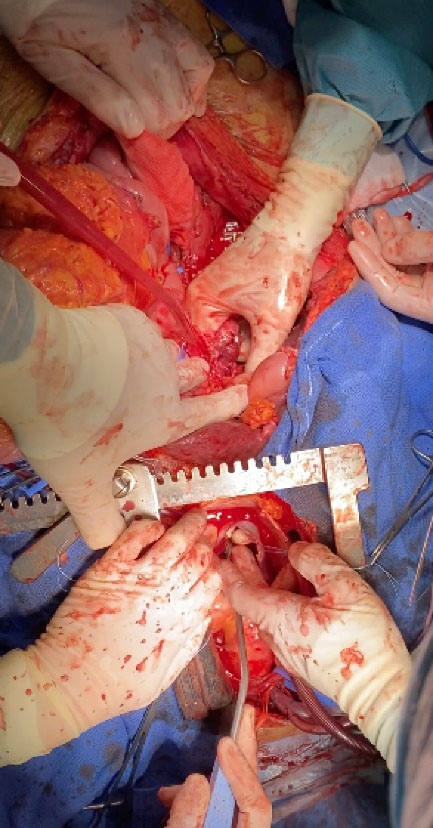

To determine the extent of the tumor, we used CT or MRI images, and performed an echocardiogram and preoperative coronary angiography depending on the indication. Figure 1 shows preoperative CT cuts of one of the patients. Tumor staging was based on the results of the different complementary tests; and the types of IVC tumor thrombi in the case of RCC and adrenal cell carcinoma were assigned according to their specific classifications.

Figure 1.

Images of the preoperative CT of one of the patients. Pathological areas are marked with an asterisk